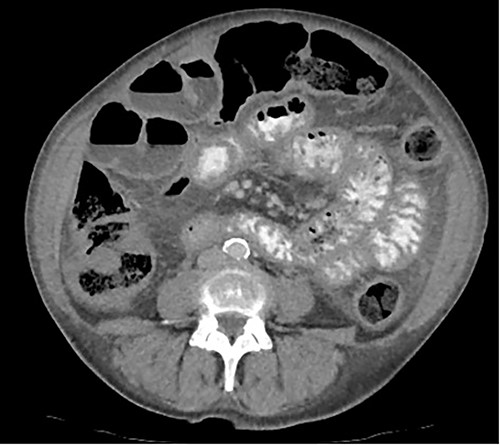

A 76-year-old lady presented to the outpatient clinic with a history of lower abdominal bloating and lethargy for 1 week. The patient denied abdominal pain, nausea, altered bowel habits or GI bleeding. Her past medical history included gastroesophageal reflux disease, ulcerative colitis and a previous hysterectomy. Physical examination exhibited pallor of the conjunctiva, distended abdomen with visible peristalsis on inspection but soft, non-tender on palpation and absence of ascites. Laboratory testing found normocytic normochromic anaemia, thrombocytosis and a positive myeloma screen with elevated kappa to lambda free light chain ratio despite normal renal and liver function. An ultrasound of the abdomen was unremarkable. Computed tomography (CT) with IV contrast of the abdomen revealed diffuse thickening of the small and large bowel with the small bowel dilated throughout. Magnetic resonance imaging of the small bowel showed multiple abnormally thickened loops of the jejunum and proximal ileum with a maximal wall thickness of 0.9 cm (Figs 1 and 2). Gastroscopy revealed severe distal oesophagitis, the stomach contained patchy telangiectasia and gastritis with sloughy mucosa at the incisura in addition to duodenitis with stricture at the second part of duodenum (D2) (Figs 3 and 4). Histopathology from the biopsies of the gastric incisura, D2 and the proximal jejunum displayed reactive changes with intramucosal haemorrhage and extensive deposition of pink amorphous, eosinophilic material on haematoxylin & eosin (H&E) stain. The deposits were predominantly seen in the proximal jejunum with a positive Congo red stain showing apple-green birefringence under polarized light (Figs 5 and 6). The patient was referred to Haematology, and a bone marrow aspirate and trephine biopsy revealed proliferation of 15% mature plasma cells consistent with the diagnosis of myeloma.

Axial CT image displaying diffuse thickening of the small and large bowel with dilatation of the small bowel.